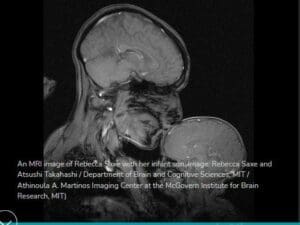

وجاءت الصورة في مقال لعالمة الأعصاب ريبيكا ساكس في معهد ماساتشوستس للتكنولوجيا، تشرح فيه لماذا قامت بأخذ صورة الرنين المغناطيسي هذه لها ولطفلها،

ذكرت العالمة أنها التقطت هذه الصورة لها ولطفلها في أبريل عام 2015، وأفادت:

في مختبري في معهد ماساتشوستس للتكنولوجيا، نستخدم التصوير بالرنين المغناطيسي لمراقبة تدفق الدم عبر أدمغة الأطفال؛ نقرأ لهم القصص ونلاحظ كيف يتغير نشاط دماغهم كرد فعل على الأحداث، من خلال القيام بذلك، فإننا نتحرى كيف يفكر الأطفال في أفكار الأخرى.على الرغم من ذلك ، لم تُصنع صورة الرنين المغناطيسي هذه لأغراض التشخيص، ولا حتى للعلم. لم يقم أحد على حد علمي ، بعمل صورة MRI لأم وطفل، لقد صنعنا هذا لأننا أردنا رؤيته.

كذلك أرشد البحث السابق إلى موقع معهد ماساتشوستس MIT للتكنولوجيا الذي نشرها بتاريخ 23/11/2015،

وأكد أنه قامت بتصويرها العالمة ريبيكا ساكس وأتسوشي تاكاهاشي (Rebecca Saxe and Atsushi Takahashi)، ولم يذكر المعهد أي معلومات عن كونها لبحث معين.

ظهر من ضمن النتائج كذلك الموقع العلمي Livescience الذي نشر الصورة مع المناطق الملونة في الدماغ وأشار أنها مناطق التعرف على الوجوه في دماغ الطفل،

وذلك في سياق مقال عن دراسة جديدة نشرت عام 2017، من معهد MIT،

تظهر أن الأطفال الذين تقل أعمارهم عن 4 أشهر يعالجون الوجوه والمشاهد التي يرونها مثل البالغين.

وأن المناطق التي تظهر كأنها نشطة في الصورة هي نتائج حقيقية بالرنين المغناطيسي الوظيفي fMRI، من الاستجابات الديناميكية الدموية أثناء النظر في أفلام الوجوه في دماغ الطفل،

وقد التقطت هذه الصورة لطفلها الأول فأردات فحص دماغه، وأن الصورة كانت بمساعدة اثنين هما Atsushi Takahashi و Ben Deen،

وأما المناطق الملونة التقطت خلال دراسة أجرتها مع الطالب دين، حول تنظيم النشاط الوظيفي في أدمغة الرضع عند عرض صور بصرية ذات مغزى، مثل الوجوه والمشاهد الطبيعية.